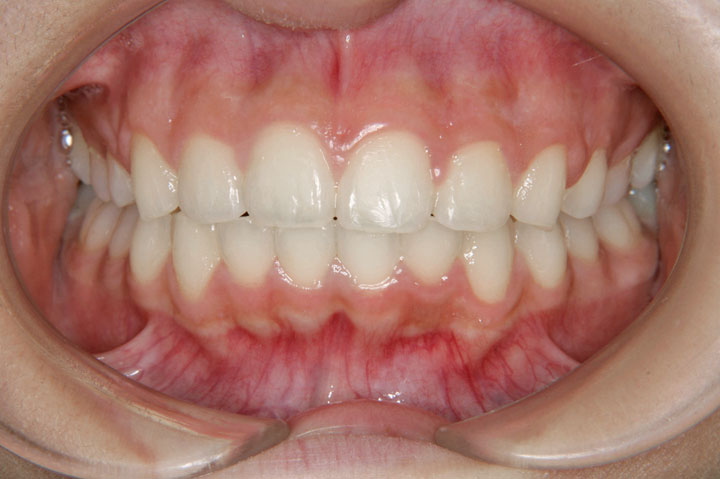

過蓋咬合(深いかみ合わせ)

叢生(乱ぐい歯)

上顎前突(出っ歯)

上顎の前突感と歯の不正を主訴に来院された中学校2年生の女子です。上顎前突、過蓋咬合、叢生などが複合する不正状態で、上顎小臼歯の抜歯をお願いしてデーモンシステムを用いたエッジワイズ治療を行いました。動的治療期間2年8ヶ月を要しましたが、装置を撤去し保定に移行しております。